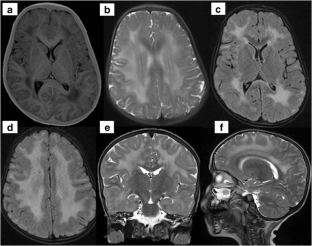

Fig. 1